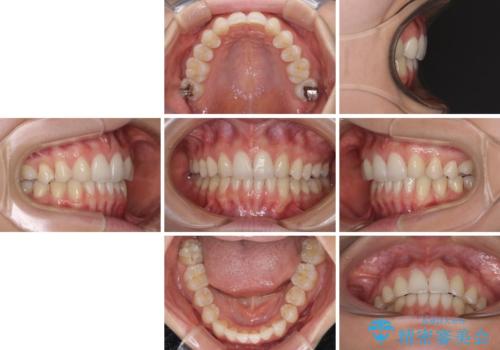

上顎前歯が2本欠損 インビザラインによる叢生の解消

- 深い咬み合わせと前歯のデコボコを気にして来院された患者様です。

上顎前歯2本が欠損しているため、妥協的なゴールを設定しインビザラインで矯正治療を行うこととしました。

上下前歯の大きさのアンバランスにより、深い咬み合わせと奥歯の咬みにくさがなかなか解決されず、治療に長期間を要することとなりました。